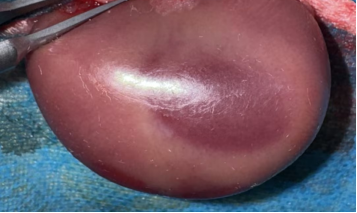

无创动脉夹夹闭肾动脉,观察肾脏转暗紫色,记录缺血时间(30-60min,可按需调整);

松开动脉夹,待肾脏恢复红润(确认再灌注成功),逐层缝合,术后青霉素抗感染。